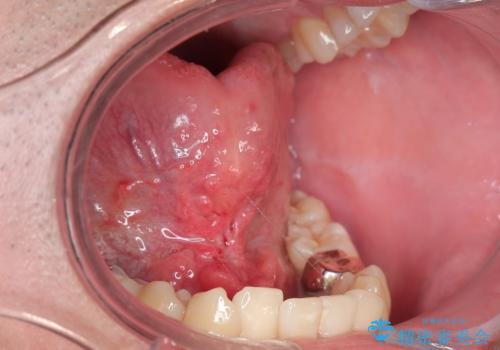

舌小帯を切りたい。

- 舌が動かしにくいと来院。

局所麻酔をし、舌小帯切除術を行うことになりました。

舌の可動範囲が広がり、満足していただけました。

舌小帯切除術は当日行うことができます。